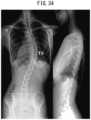

FIG.34 is an X-ray photograph of a patient with thoracic idiopathic scoliosis; and

In contrast, in a control case, a patient developed thoracic AIS and the apex of MT scoliosis was at T9 as illustrated inFIG.34. The postoperative apex of the TK of the patient was at T9 as illustrated inFIG.35, which is almost identical with the preoperative apex (T9) of scoliosis. The postoperative “non-anatomical” TK is considered to be created by the procedure of rod bending so as to approximate the curvature of the rods to the curvature of scoliosis of the spinal column before correction, and by attaching the rods to the spinal column of the patient and rotating the rods. Note that the shapes of the rods used in the control case were different from the shapes of the above-describedfirst rods100 and thesecond rods200. In this way, using the rods that were bent to approximate the curvature of the rods to the curvature of scoliosis of the spinal column before correction, the apex of the TK of the patient became T9 that was almost identical with the preoperative apex (T9) of thoracic scoliosis, exhibiting a gibbus like condition instead of an anatomically normal spinal column arrangement.